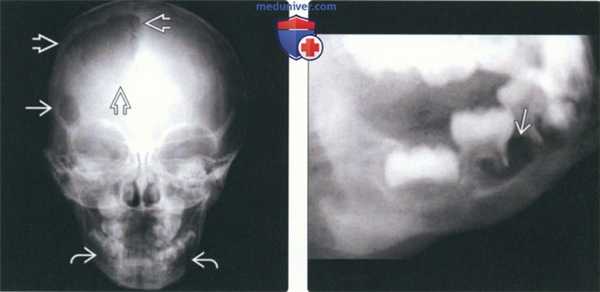

(Слева) На рентгенограмме черепа в прямой проекции визуализируются два очага ЛКГ в лобной кости: меньший (округлый с ровными контурами) и больший (неправильной формы). Для описания подобных поражений используется термин «географический череп». Очаги также определяются в нижней челюсти.

(Справа) На рентгенограмме в косой боковой проекции у этого же пациента определяется «выскобленный» очаг вокруг мезиального корня формирующегося 1-го моляра. Пациент страдает хроническим диссеминированным ЛКГ, клинически проявляющимся экзофтальмом.